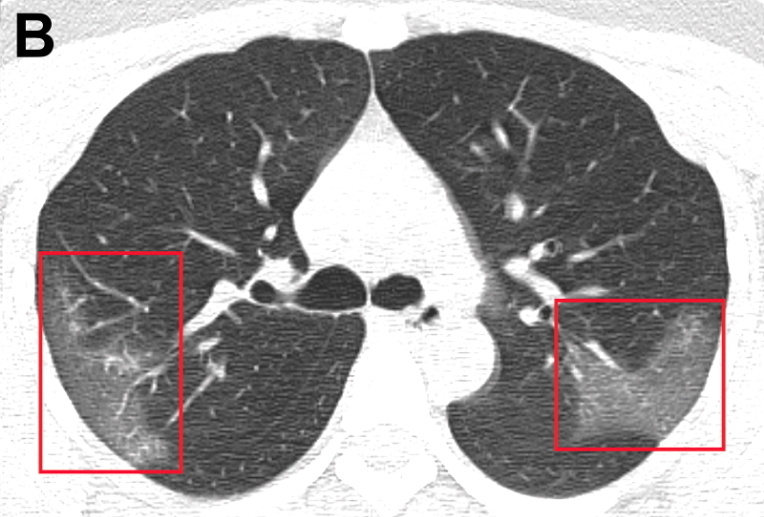

Factores pronósticos en pacientes internados con COVID-19

Los principales indicadores de un mal resultado fueron la edad avanzada, el puntaje SOFA elevado y un valor de dímero-d al ingreso > 1 μg/L. The Lancet, 9 de marzo de 2020